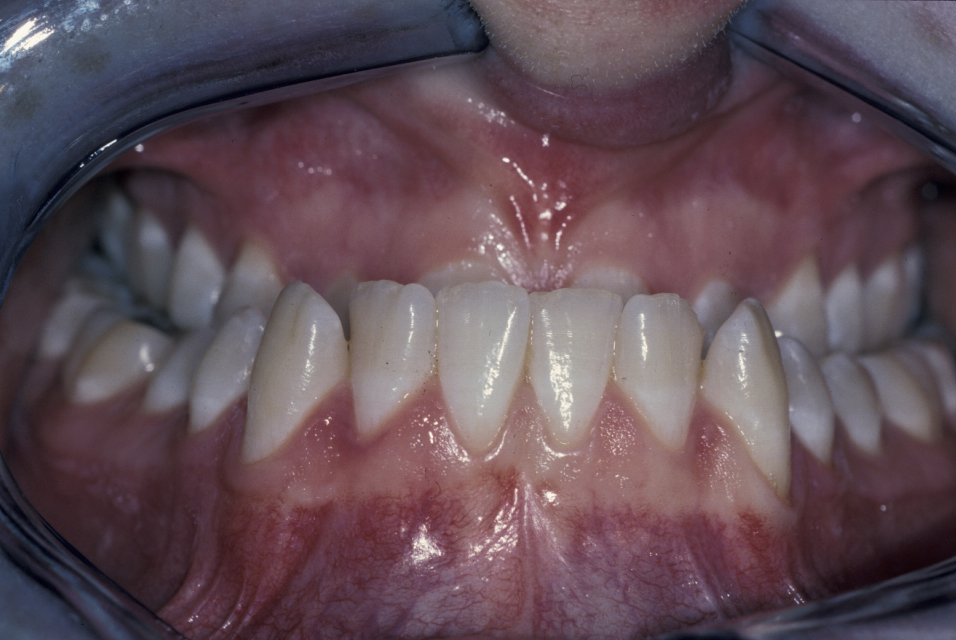

The molar and incisal relationships are examined visually and are formally documented by photographs (see Figure 5, Figure 6 and Figure 7 for examples) and study models (see below).

Figure 5: Intraoral view showing a class III malocclusion (underbite).

Figure 6: Intraoral view showing a class III malocclusion (underbite).

Figure 7: Intraoral view of a class III malocclusion (underbite).